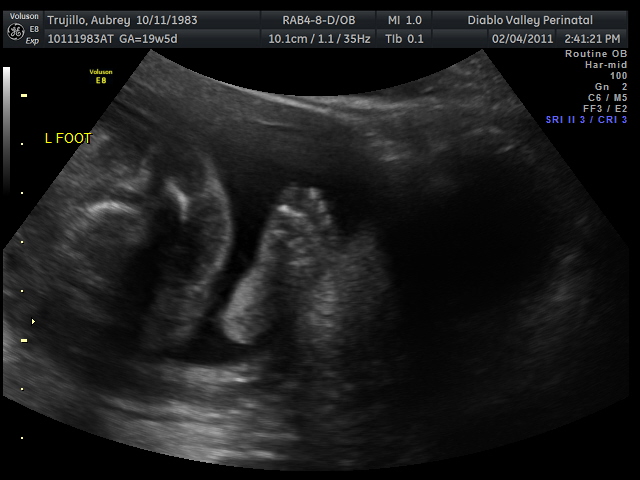

20 weeks - profile20 weeks - Profile again20 weeks - Right foot!20 weeks - sucking thumb!!!!20 weeks - hand near face20 weeks - flexing his bony arms!20 weeks - hiding from mommy and daddy!20 weeks - it's a boy!33 weeks - 3D!33 weeks - 3D!33 weeks - 3D!